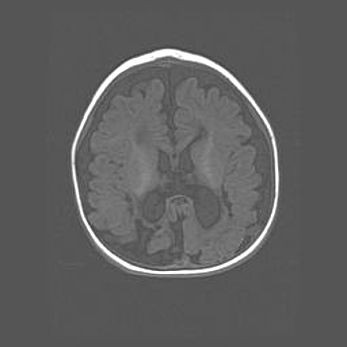

Церебральная ишемия II.

Возраст: 7 дней

Вес: 3350 г

Пол: женский

Окружность головы: 35 см

Срок гестации: 39 недель

Ишемия головного мозга – это состояние, которое развивается в ответ на кислородное голодание вследствие недостаточного мозгового кровообращения. У новорожденных она является следствием дефицита кислорода, что ведет к метаболическим расстройствам различной степени тяжести в тканях головного мозга, в том числе к развитию коагуляционных некрозов и гибели нейронов.